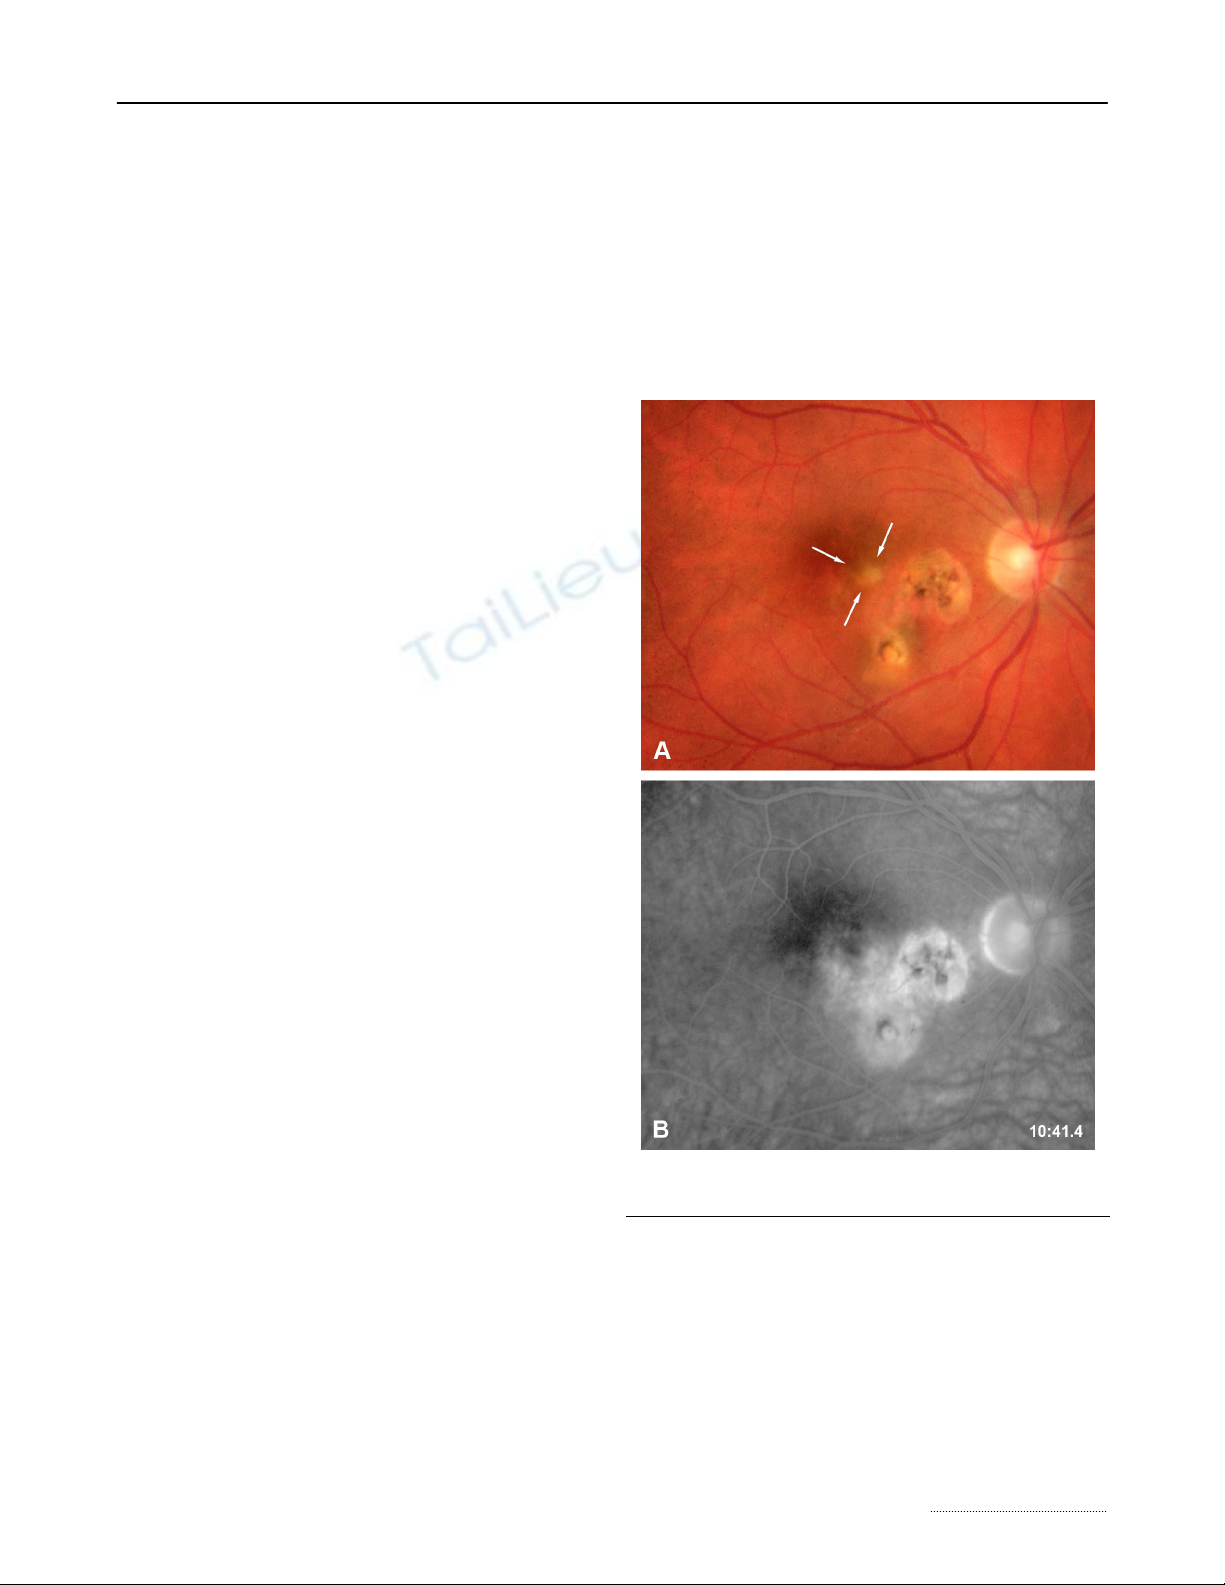

Ocular toxoplasmosis is the most frequent cause

of posterior uveitis. [1] The parasite has an intracel-

lular cycle. During the primary infection, the subject is

usually asymptomatic and can present flu-like

symptoms. A dissemination of the parasites occurs

and the tissular cysts will persist during the all life of

the host. An ocular reactivation of the disease can

occur when the cysts are present within the retina

(Figure 1). The patients present a photophobia and

floaters are seen. The slit-lamp examination reveals

the presence of a granulomatous inflammation, a mild

to moderate anterior chamber inflammation. Fundo-

scopy reveals the presence of a yellow focus of reti-

nochoroiditis. Recent epidemiological data have

Figure 1: Active retinitis area adjacent to previous cica-

tricial foci.